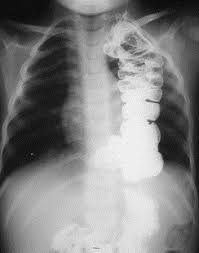

The Shaggy Esophagus Springerlink

The Shaggy Esophagus Springerlink from media.springernature.com

Behr j, kreuter m, hoeper mm, wirtz h, klotsche j, koschel d, andreas s, claussen m, grohé c, wilkens h, randerath w, skowasch d, meyer fj, kirschner j. A recent review reveals 56 documented cases in the literature. Animals with mild esophagitis generally have a favorable prognosis. B from levine ms, woldenberg r, herlinger h, et al. Esophagitis may cause odynophagia and even esophageal hemorrhage, which is usually occult but can be massive. Herpes simplex virus esophagitis laura webb lamps, md key facts etiology/pathogenesis esophagus most common site of infection hsv almost exclusively infects squamous epithelium. Department of radiology of the loyola university medical center, usa. Hsv esophagitis has been described in immunocompetent hosts, however, it remains a rare entity.